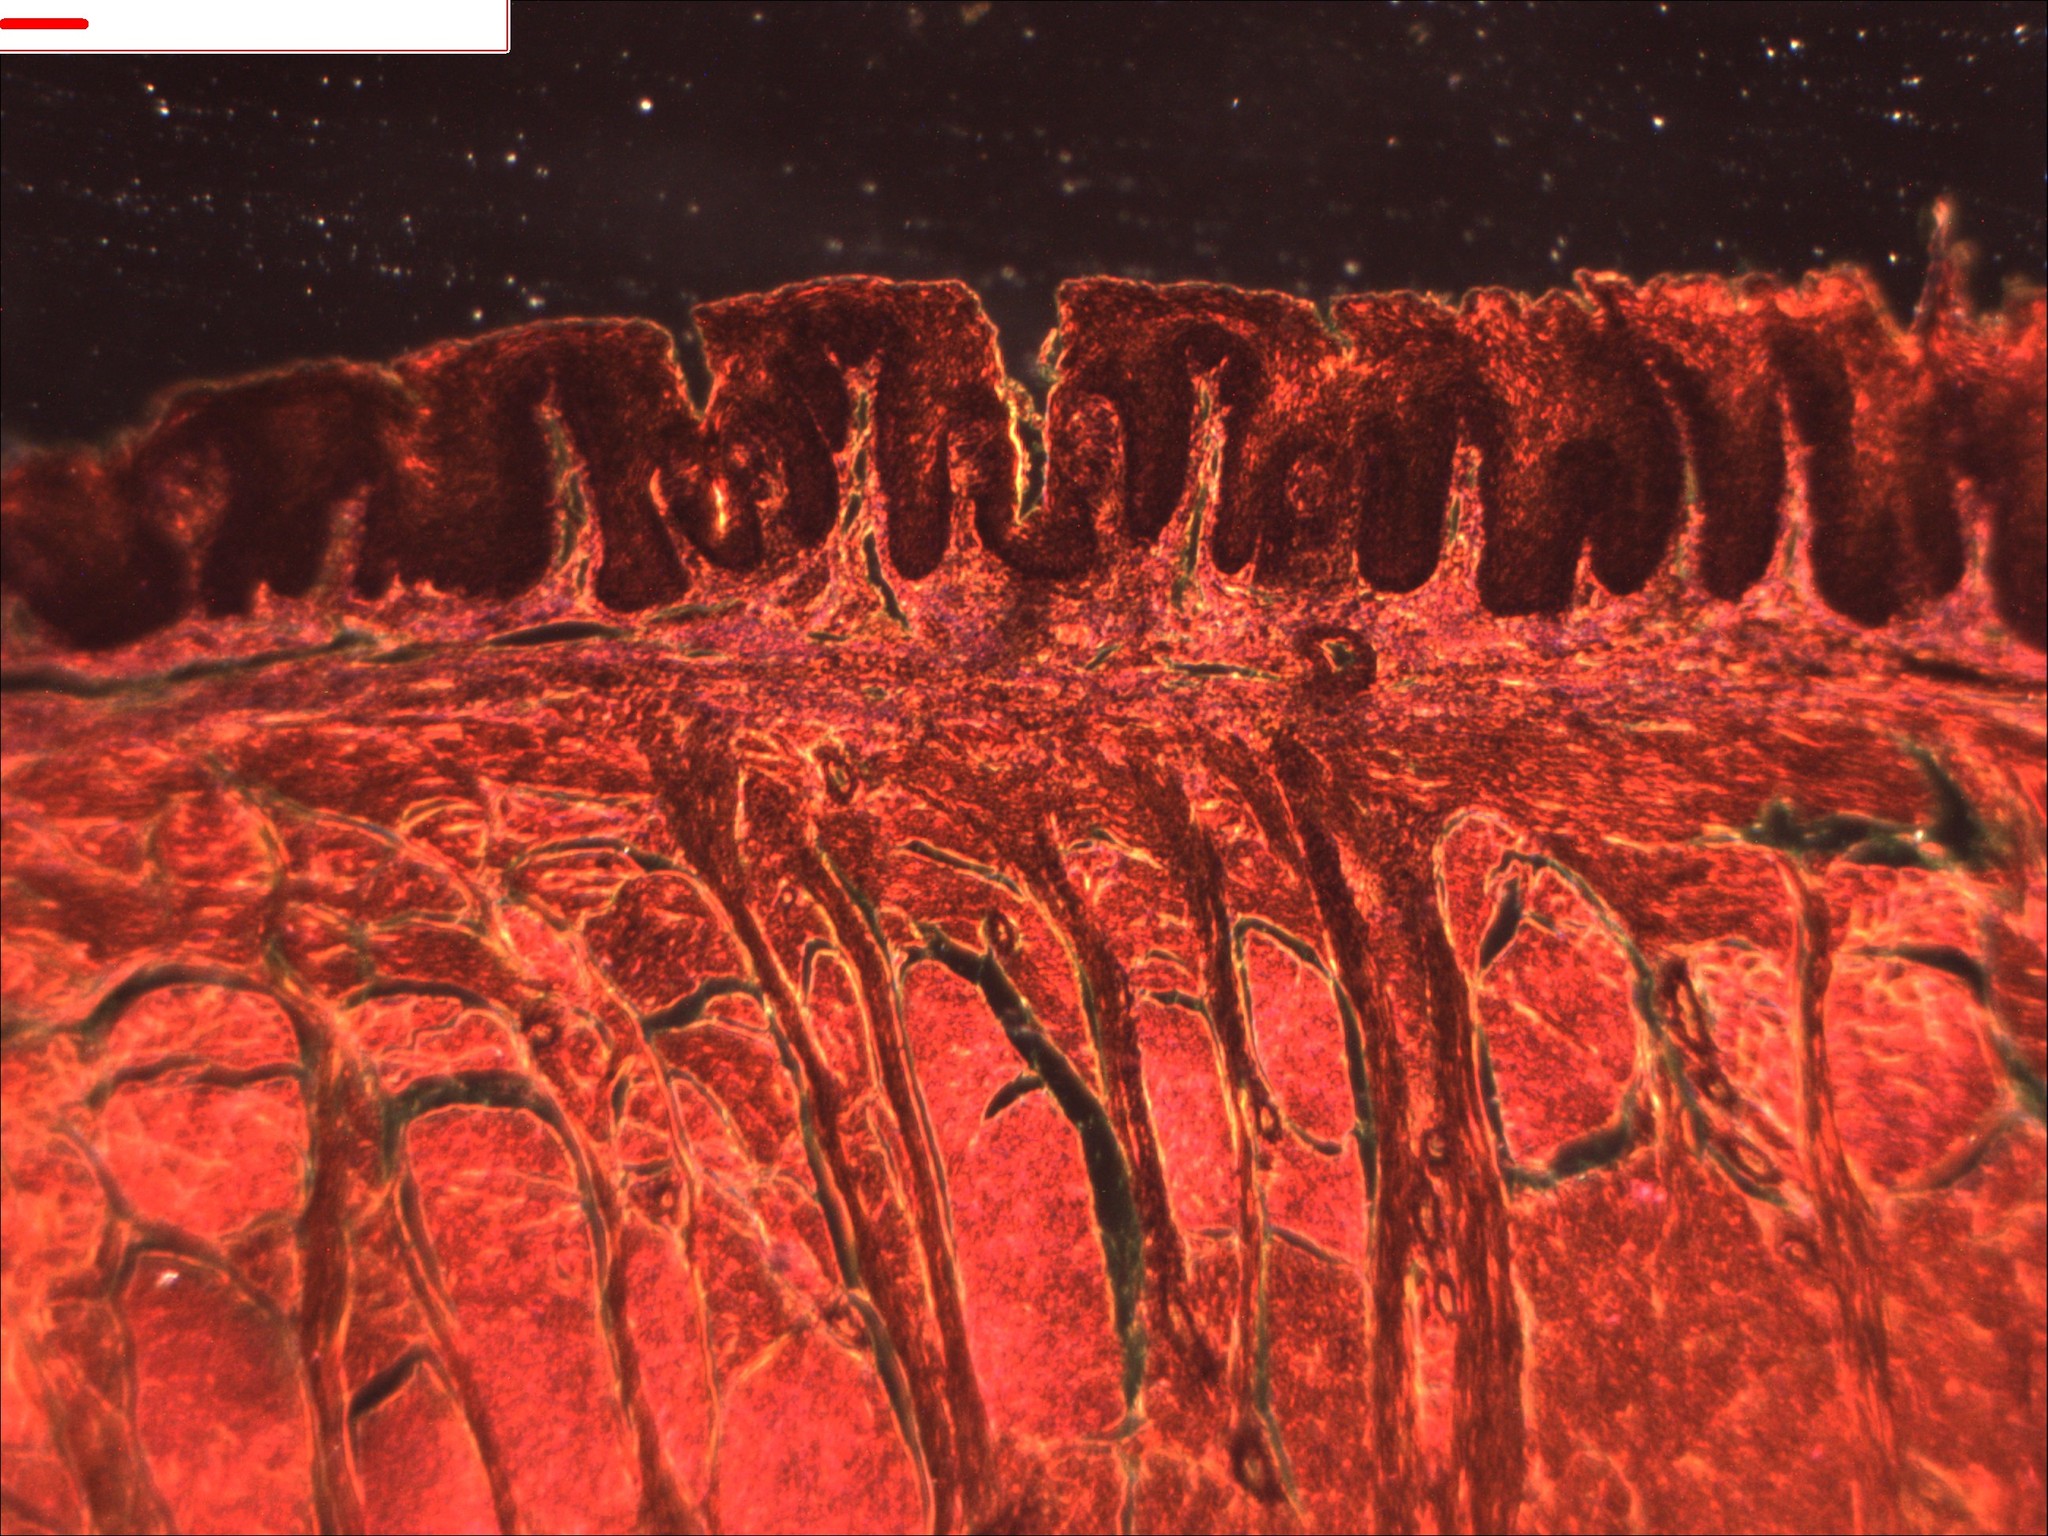

1 DELETED Лига любителей макрофото Вкусовые рецепторы человека 5 лет назад Метод наблюдения "Тёмное поле" [моё] Микроскоп Макро Макросъемка Человек